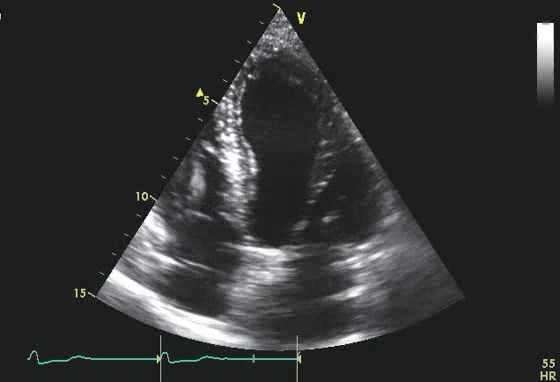

М-режим эхокардиографии является полезным в документировании асимметричного утолщения межжелудочковой перегородки, передне-систолического движения передней створки митрального клапана, и среднесистолического прикрытия аортального клапана. Непропорциональная септальное утолщение миокарда проявляется также в ПЖ и нижней стенки миокарда. Передне-систолический ход створок митрального клапана можно увидеть и в прочих гипердинамических кардиальных условиях. Двумерная (2D) эхокардиография остается главным подходом выбора для установления диагноза гипертрофическая кардиомиопатия. Кроме того, подробная морфологическая характеристика обеспечивается 2D эхокардиографической визуализацией. Наиболее частой из морфологического разнообразия выявляется гипертрофическая кардиомиопатия, которая состоит из диффузного утолщения желудочков, перегородки и переднебоковой свободной стенки (70%-75% случаев). Гипертрофия, которая сопровождается утолщением базальной зоны межжелудочковой перегородки (10%-15% случаев), концентрическая гипертрофия (5% случаев), апикальная гипертрофия (

Верхушечная гипертрофическая кардиомиопатия могут быть пропущены на 2D эхокардиографии, если осмотр верхушечной зоны осуществляется неопытным врачом. Обследование из парастернальной позиции не может обеспечить диагноз, так как гипертрофия обычно сводится к верхушке. Из-за массивной апикальной гипертрофии и движения эпикарда можно ошибочно предложить дискинезию верхушки (что иногда вызывает ложную диагностику апикальной аневризмы), но движения эндокарда показывает практически полную облитерацию полости верхушки. Внутривенное введение контрастного вещества при эхокардиографии, является чрезвычайно полезным в определении малой полости верхушки с конфигурацией «туз пик», свойственной для апикальной ГКМП.